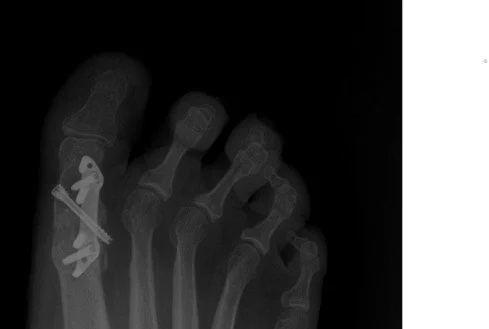

4. Arthrodesis (Fusion)

• Gold standard for advanced arthritis (AOFAS/ACFAS consensus)

• 95% union rates, durable pain relief beyond 10 years⁷

Modern options:

• MIS Fusion (Stryker platform): Keyhole access, less dissection, fluoroscopic control

• Treace First MTP Fusion System: Low-profile contoured plate with crossing screws, designed for anatomic alignment and earlier weightbearing

ap xray of a 1st mpj arthrodesis using treace speed plate 1st mpj arthrodesis plating system